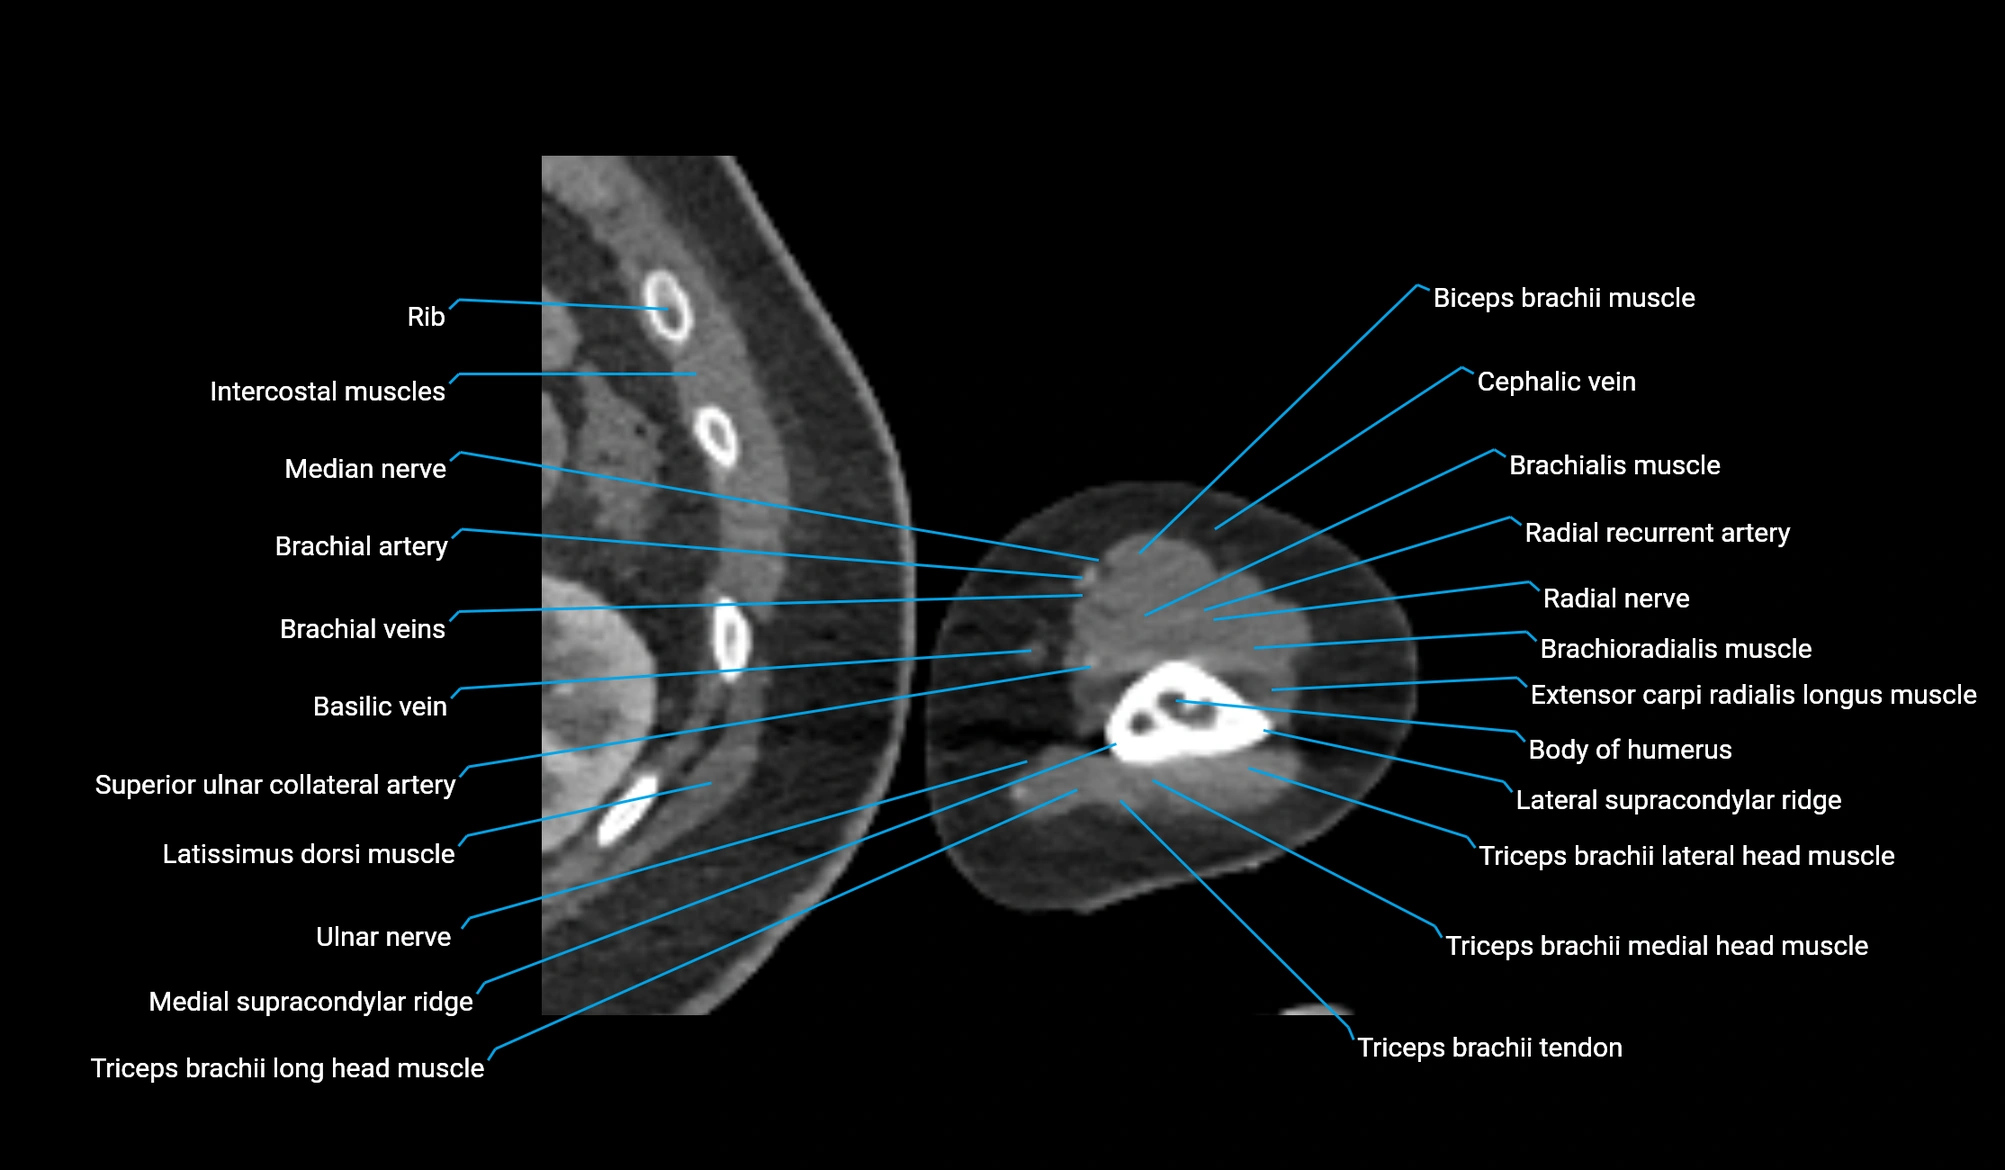

- Body of humerus

- Biceps brachii muscle

- Brachialis muscle

- Cephalic vein

- Brachial artery

- Brachioradialis muscle

- Extensor carpi radialis longus muscle

- Extensor carpi radialis brevis muscle

- Lateral supracondylar ridge

- Medial supracondylar ridge

- Lateral head of triceps brachii muscle

- Medial head of triceps brachii muscle

- Long head of triceps brachii muscle

- Triceps brachii tendon

- Radial nerve

- Radial recurrent artery

- Superior ulnar collateral artery

- Basilic vein

- Median nerve

- Ulnar nerve

- Latissimus dorsi tendon